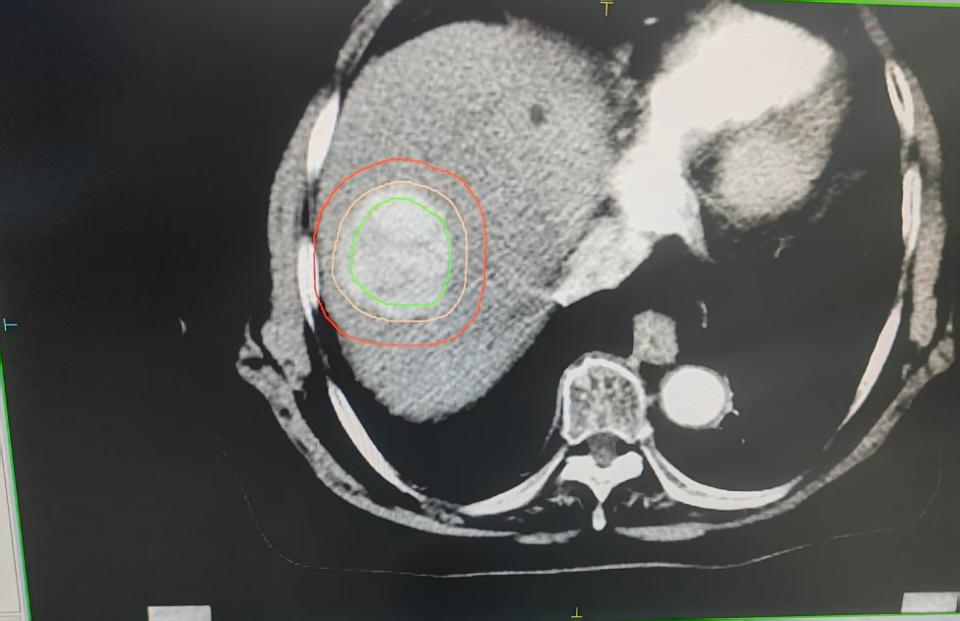

HCC患者入院时CT增强影像学特征

注:图A、B是术前2026年1月26日CT增强影像。影像显示肝左叶占位(95×11 mm),考虑肿瘤,并提示破裂出血可能。